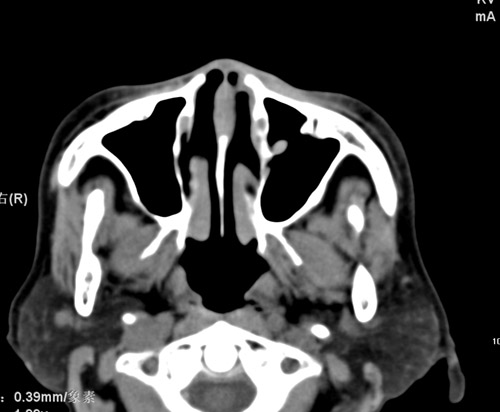

标题: CT17755:女,74 左鼻旁肿胀半年,临床以左上颌窦旁占位行CT [打印本页]

标题: CT17755:女,74 左鼻旁肿胀半年,临床以左上颌窦旁占位行CT

ct考虑鼻前庭囊肿 或鼻翼基底部慢性炎症,左上颌窦少许炎症 请指教

1)考虑左侧鼻前庭囊肿并感染。2)双侧上颌窦炎。

左侧鼻前庭囊肿并感染。双侧上颌窦炎。支持